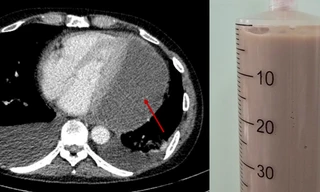

Trung tâm Tim mạch - Bệnh viện Đa khoa Quốc tế Vinmec Times City vừa thực hiện thành công ca thay van động mạch chủ qua da (TAVI) với giải phẫu đặc biệt phức tạp, dưới sự hỗ trợ của công nghệ in 3D cá thể hóa. Đây là lần đầu tiên tại Việt Nam, mô hình 3D được ứng dụng trong toàn bộ quy trình lập kế hoạch can thiệp TAVI, giúp các bác sĩ mô phỏng chính xác cấu trúc tim, dự đoán biến chứng và tối ưu hóa chiến lược can thiệp ngay từ bước chuẩn bị.